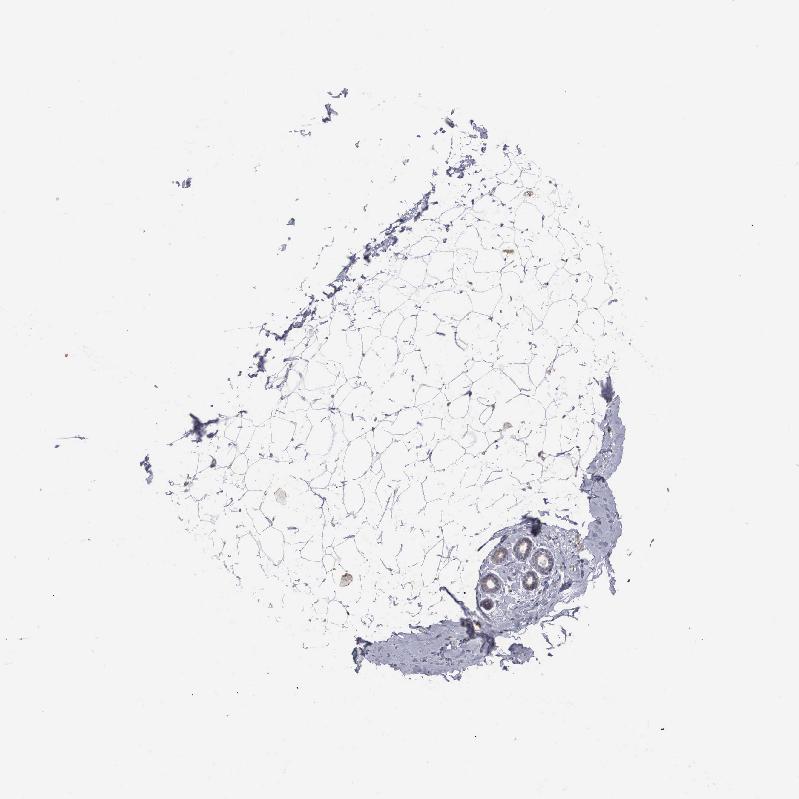

ADIPOSE TISSUE - Antibody stainingi

Antibody staining in the annotated cell types in the current human tissue is reported as not detected, low, medium, or high, based on conventional immunohistochemistry profiling in selected tissues. This score is based on the combination of the staining intensity and fraction of stained cells.

Each image is clickable and will lead to virtual microscopy that enables deeper exploration of all samples and also displays staining intensity scores, fraction scores and subcellular localization as well as patient and tissue information for each sample.

Antibody HPA000251

Adipocytes Not detected